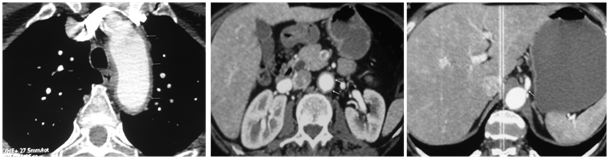

Laboratory tests showed hemoglobin 8.5 g/dl, white blood cell count 10250/mm3, erythrocyte sedimentation rate was 124 mm/hour, and level of C - reactive protein was 59 mg/l, serum fibrinogen concentration 5.4 g/l, serum albumin level 36 g/l and an increased serum globulin 16.8 g/l. Other laboratory tests, especially the lipid profile were within the normal range. Microbiological cultures were unremarkable. A computed tomography scan revealed an ascending aortic thickening of the thoracic, abdominal aortic wall and celiac trunk with periaortic inflammation extending to the iliac arteries (Figure 1). It also disclosed bilateral subclavian artery stenosis. There was no aneurysm or dissection.

Figure 1 (a) A computed tomography scan revealed an ascending aortic thickening of the thoracic, abdominal aortic wall (b) and celiac trunk (c) with aortic inflammation extending to the iliac arteries.

Our observation further shows that GCA might be borne in mind as a cause of acute coronary syndrome and aortitisin patients over 50 years with extracardiac symptoms and biological inflammation. Temporal artery biopsy should be performed in patients over age 50 years with myocardial infarction; aortitis when biological inflammation is proved, even in the absence of suggestive clinical signs (Figure 1).